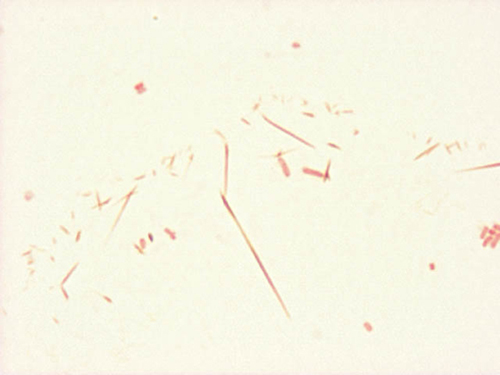

Safranin crystals #1

Gram stain artifact

In addition to the Gram positive cocci, this Gram stain has residual safranin crystals. Note the thin red crystals, which are very long in the center of the image, to very small in the surrounding areas. The presence of safranin crystals are due to an inadequate rinse of the slide at the end of the Gram stain procedure.